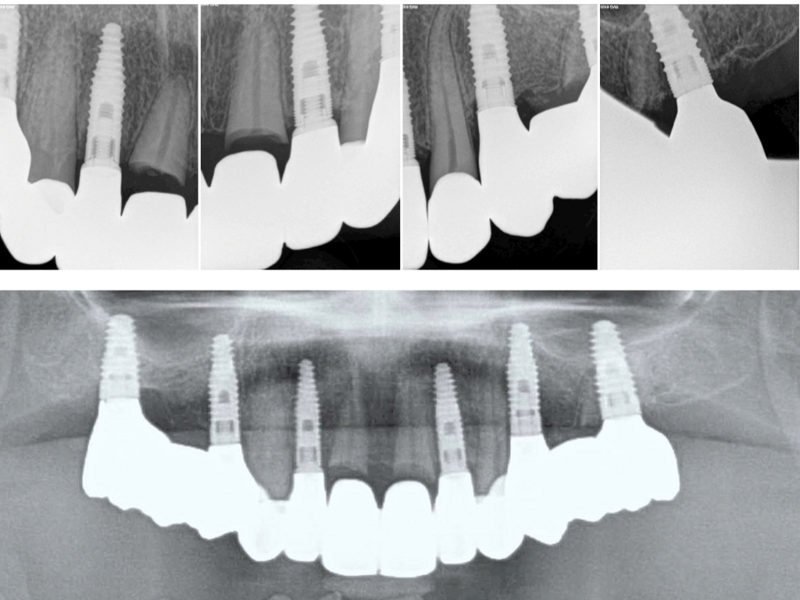

Both surgical interventions were performed under local anaesthesia, and antibiotic medication (a single dose of 2 g of amoxicillin) was administered 60 minutes before surgery. The first stage of rehabilitation of the maxilla involved immediate implant placement in the post-extraction sockets of both lateral incisors in combination with the socket shield technique for the right lateral incisor. Owing to an increased tooth mobility of more than Grade II, the socket shield technique was contra-indicated for the left lateral incisor and both premolars. The clinical crowns of both central incisors were decapitated, and the roots were carefully prepared with a round diamond bur under rinsing with sterile saline solution, until both cranial root edges reached a distance of 3 mm from the gingival margin (Fig. 5). In the right lateral incisor site, a socket shield was prepared as described by Gluckman et al.12 The extracted premolars were mechanically cleaned and then dried and processed with the Smart Dentin Grinder (KometaBio) according to the manufacturer’s recommendations.13 After implant site preparation, particulate dentine was applied into the prepared left lateral incisor implant site, and both extraction sockets of the left premolars (Fig. 6). Implant placement was performed in the extraction sites of both lateral incisors with two BEGO Semados RSX implants (BEGO Implant Systems) with a length of 13.00 mm and a diameter of 3.75 mm (Fig. 7). Peri-implant gaps were grafted with particulate dentine autograft and sealed with platelet-rich fibrin (PRF) membranes using the Poncho technique.14 After buccal and palatal tunnel preparation, the premolar extraction sockets and submerged left central incisor root were covered with PRF membranes, prepared according to the Choukroun method (A-PRF, mectron) after centrifugation at 1,300 rpm for 13 minutes.15 The right central incisor was covered with a connective tissue graft harvested from the palatal mucosa of the first quadrant. Covering membranes and the connective tissue graft were introduced into the buccal and palatal tunnel preparations and fixed with absorbable monofilament #5/0 suture thread (Serafast, Serag Wiessner; Fig. 8). The postoperative radiograph showed adequate root submersion of the central incisors, correct implant positioning in the lateral incisor sites and proper filling of both premolar extraction sockets (Fig. 9). The patient was provided with the fixed provisional bridge (Fig. 10) and prescribed amoxicillin (1 g three times a day for five days after surgical intervention). Postoperative healing was uneventful.

Fig. 9: Radiograph after first-stage surgery.

Definitive prosthetic treatment was performed after completion of implant healing with three CAD/CAM-fabricated monolithic zirconia bridges (DD cubeX2, Dental Direkt). The bridges were screwed on to BEGO titanium base abutments (Figs. 14–16). Good fit of the prosthetic superstructures was displayed in the radiograph after placement (Fig. 17). The two-year follow-up examination in July 2019 revealed excellent aesthetic and clinical soft-tissue conditions (Figs. 18–20). No radiographic bone loss had occurred at the implant sites (Fig. 21). Neither the submerged central incisors nor the distobuccal molar root displayed any signs of periapical inflammation, and the patient reported no complications. The patient’s oral hygiene had improved significantly during the follow-up period.

Fig. 17: Final radiograph with definitive prosthetic superstructures in place.

Fig. 21: Radiographic control after the two-year follow-up period, showing no visible bone loss at the implant sites and no signs of periapical inflammation at submerged roots.